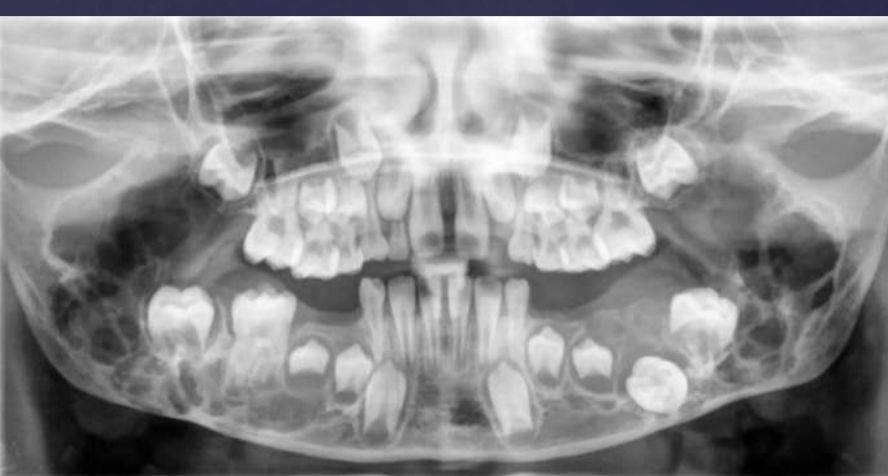

T/F: you can see B/L expansion in this radiograph

false, since this PAN is a superimposed image- you cannot tell